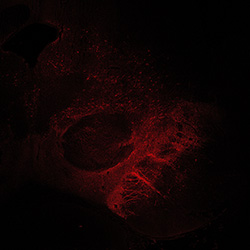

An anatomical analysis of the developing human midbrain from 6 post-conceptional weeks (PCW) to 22 PCW reveals increased tissue complexity, characterized by the emergence of dopaminergic nuclei, as highlighted by immunofluorescence analysis for tyrosine hydroxylase (TH).

TH

6PCW human midbrain